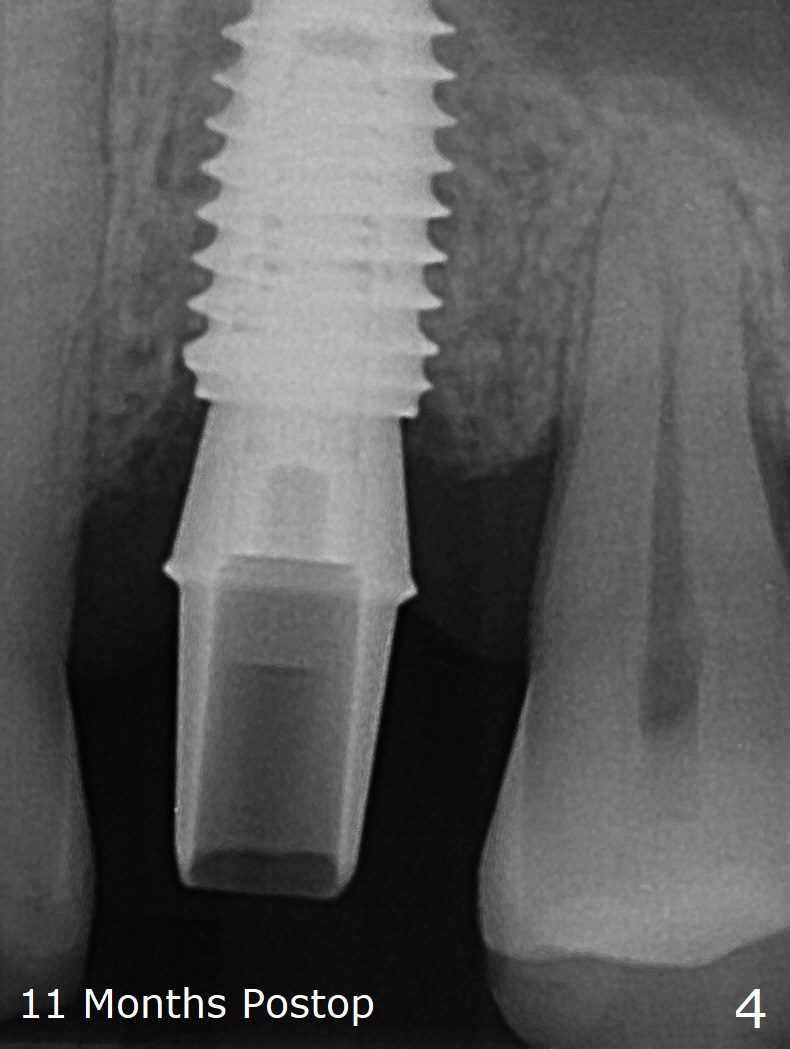

In fact the designed initial drills do not get to the bone with guides. After use of the next length drills (1.5 mm longer with sharp end), the sinus floor perforates without membrane perforation. Once 3.5 mm drill is used following sequential osteotomy, a 4x10 mm dummy implant is placed for sinus lift with 1 mm short of the depth and >50 Ncm. Following the dummy implant removal, allograft in the amount of 2 to 3 amalgam carriers is delivered for sinus lift (Fig.1,2 white *), followed by implant placement (4.5x10 mm, >55 Ncm). More allograft is placed before and after abutment insertion (black *). As usual, an immediate provisional is fabricated at each site. After removal and cleaning, the abutments are reseated and retorqued to 30 Ncm 11 months postop (Fig.3,4). Sinus lift is indistinct 15 months postop (Fig.5,6), probably due to radiation overexposure, although placement trajectory is good.